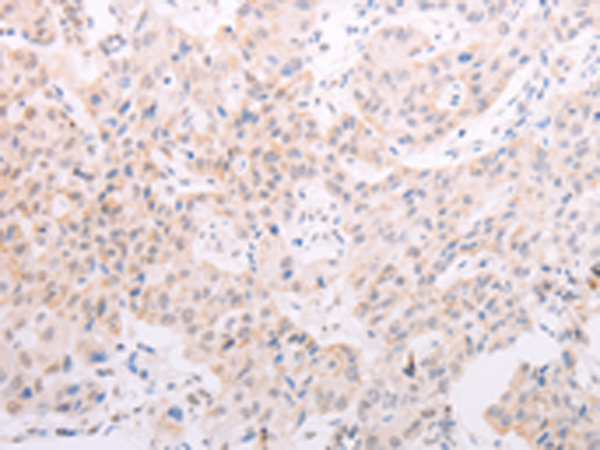

分类: 科研抗体货号: P07679别名: RNF84; MGC:39780应用: IHC反应种属: Human, Mouse